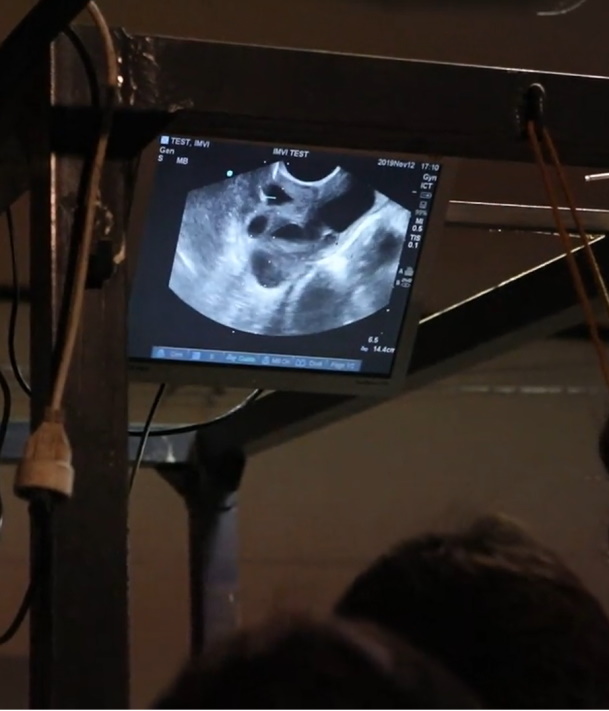

Ovum Pick-up

A recolha de oócitos é um procedimento invasivo, porém vantajosoo para garanhões sub-férteis ou para garanhões que tenham poucas reservas de sémen.

É um procedimento que se pode realizar em caso de morte súbita da égua e que o proprietário queira tentar preservar a sua genética.

Pode-se realizar em éguas com problemas reprodutivos que de outra forma não conseguiram gerar produtos.